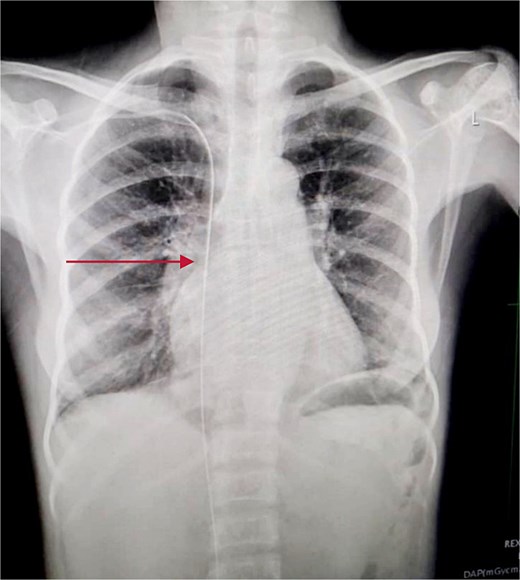

An immediate chest X-ray revealed the metallic guide wire within the right hemithorax, coursing from the anterior medial aspect of the cupola to the posterolateral aspect of the second intercostal space, with a notable curve at the diaphragm (Fig. 2).

Chest X-ray posterior anterior and lateral view showing the intrathoracic metallic guide. The wire’s thin, linear shape is clearly visible, with an abrupt change in course around the cupola indicating its unintended migration from the subclavian vein into the chest cavity.